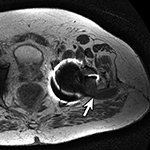

Adverse reaction to metal debris with posterior pseudotumor. Axial T1-weighted fast spin echo (FSE) (A) and STIR (B) MR images demonstrate left peritrochanteric fluid collection (arrow in A and arrowheads in B) arising from the left hip joint in a patient with metal-on-metal hip arthroplasty. Note the thin low T2 signal rim surrounding the fluid collection representing metal deposition. |